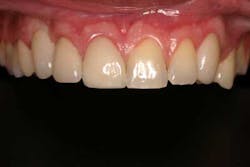

A 37-year-old male with a noncontributory medical history, taking no medications with no known food or drug allergies, presents to the office with a chief complaint of “I don’t like the way my upper right bridge looks.” His dental history includes extraction of tooth No. 6 two years ago due to a failed root canal and recurrent decay deemed restoratively hopeless. He was temporized one year after extraction with an acrylic bridge from teeth Nos. 5 to 7. Socially, he denied tobacco, drug, and alcohol use. The patient complained of color match, overcontoured bulkiness, and the inability to perform adequate oral hygiene.

Treatment options were reviewed with the patient and because of hygiene considerations, a single-tooth restoration in site No. 6 with single-unit crowns on No. 5 and No. 7 was chosen over a porcelain-fused-to-metal fixed bridge from Nos. 5 to 7. Clinical records were taken, which included preoperative radiographs, a cone beam CT scan, and a diagnostic wax-up. From the diagnostic wax-up, a surgical index was created and used during dental implant placement. Since the site had been edentulous for two years and based on the results of the CT scan, a buccal concavity was noted at the apex of No. 6. After local infiltration, a midcrestal incision was made with papilla sparring incisions. No vertical releases were performed.

Using the surgical index as a reference, a 3.8 x 12 tapered implant was placed in a prosthetically driven manner. During placement, a 3 x 3 mm fenestration of the buccal plate occurred at the apical extent of the implant. Using a combination of enamel matrix derivate mixed with cortico-cancellous allograft placed in a bone syringe, the area of fenestration was grafted. Although the implant achieved 35 Ncm of stability, a cover screw was placed and primary coverage was achieved. A conventional two-stage procedure was selected because of the regenerative demands of this particular case. The area was then temporized with a newly fabricated lab-generated acrylic bridge with careful attention to pontic site development.